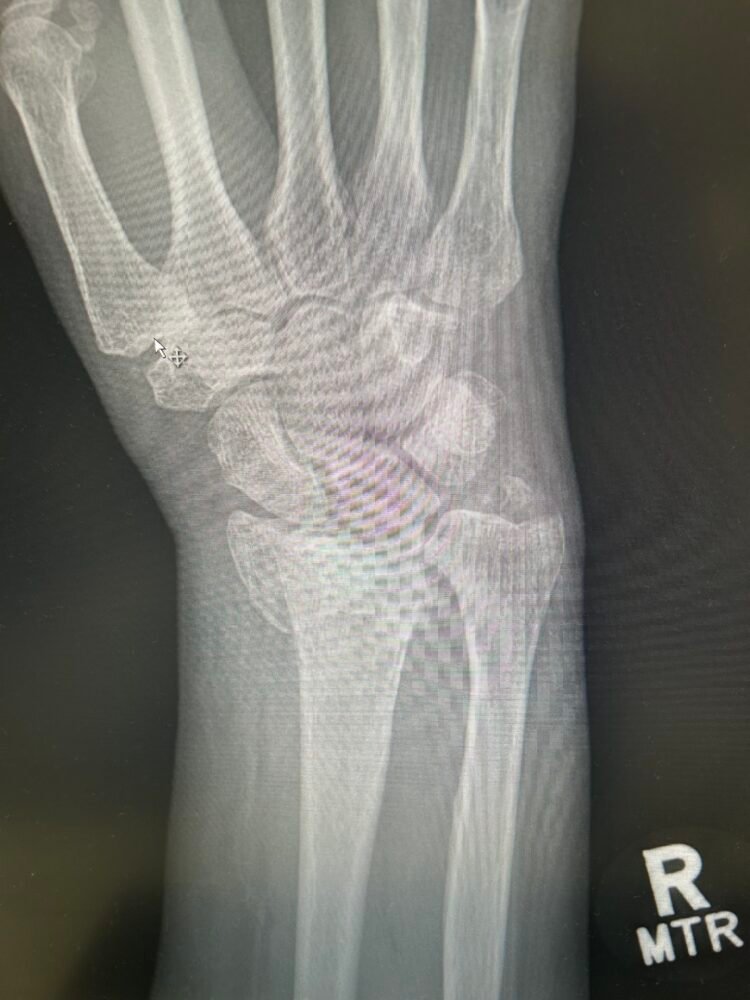

The title of this post mentions a glitch and that would be that I had a fall and broke my wrist quite badly and needed surgery to insert plates . This has meant that I have not been able to do any of the packing up and removal of the kitchen. It is extremely frustrating to say the least.